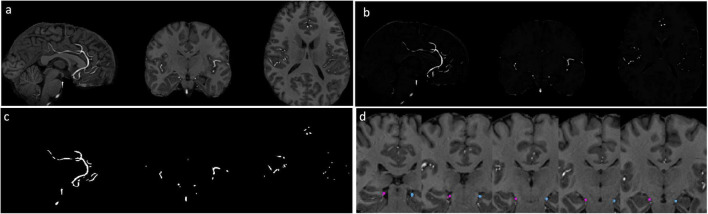

Methods: In this study, 191 participants (aged 30-59 years, 115 female) underwent 7T MRI to segment hippocampal supply vessels and hippocampal volume from T1-weighted images. Twenty-three systemic parameters related to the metabolic syndrome, autonomic function, inflammation, vascular stiffness, and endothelial function were measured at rest. Mediation analysis examined whether hippocampal vessel velocity and size mediated the relationship between systemic factors and hippocampal volume.